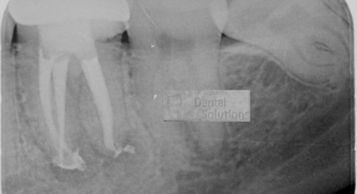

Improved lighting and magnification aid in caries detection and removal.

Improves detection and evaluation of coronal and root fractures and abnormalities.

Better vision is necessary for any dental Treatment. Root canal under microscope gives us